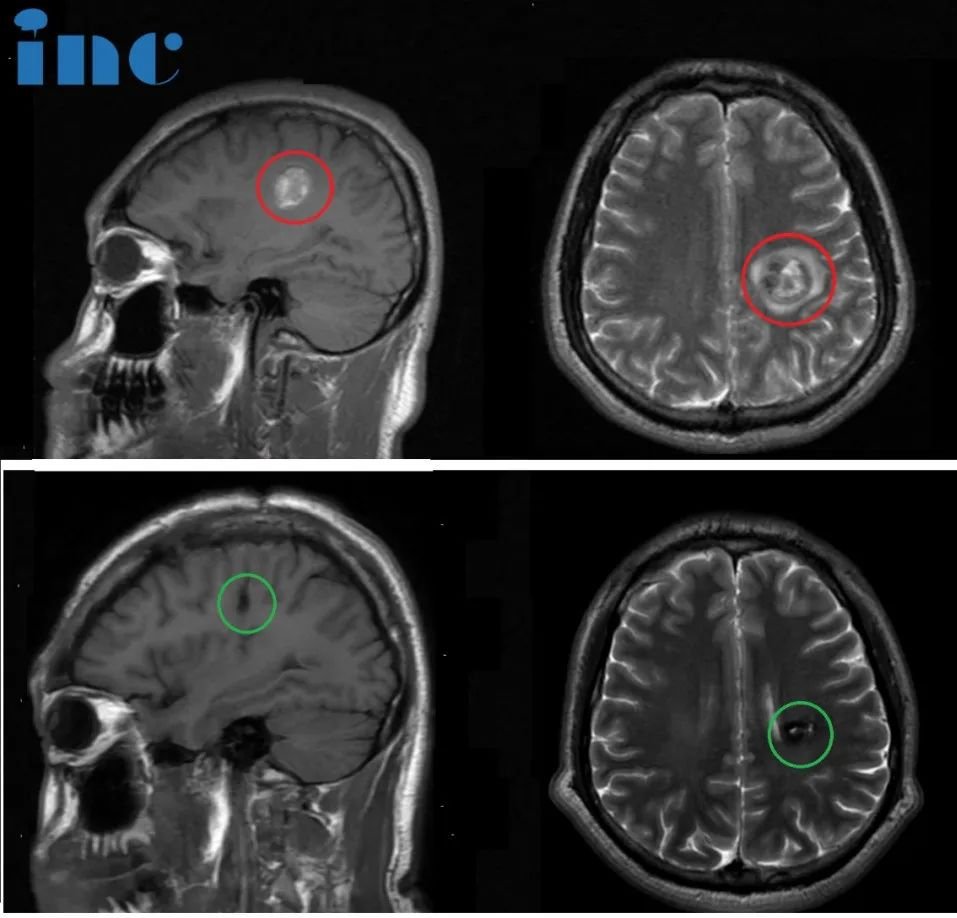

23岁男孩-半卵圆中心海绵状血管瘤

简要病史:23岁的彦文一年前感觉右手无力,写不了字,5月份就医检查左半卵圆中心海绵状血管瘤,住院治疗一周,期间右腿、右脚无力,走路不利索,医院给予保守治疗后出院。彦文父母一直苦苦寻求能为年轻的孩子顺利手术的主刀医生。今年4月,他们看到了国际神外教授巴教授来华示范手术消息,于是奔赴苏州寻求教授为孩子主刀手术。

治疗过程:4月9日,在苏州独墅湖医院,巴教授已经顺利为彦文顺利完成手术,全切左半卵圆中心海绵状血管瘤。

术后情况:术后一周,已经可以自行下床活动,术后的右手麻木等症状有所缓解,术后两周多顺利出院,术后两个月,可以正常行走骑自行车,基本恢复正常生活。